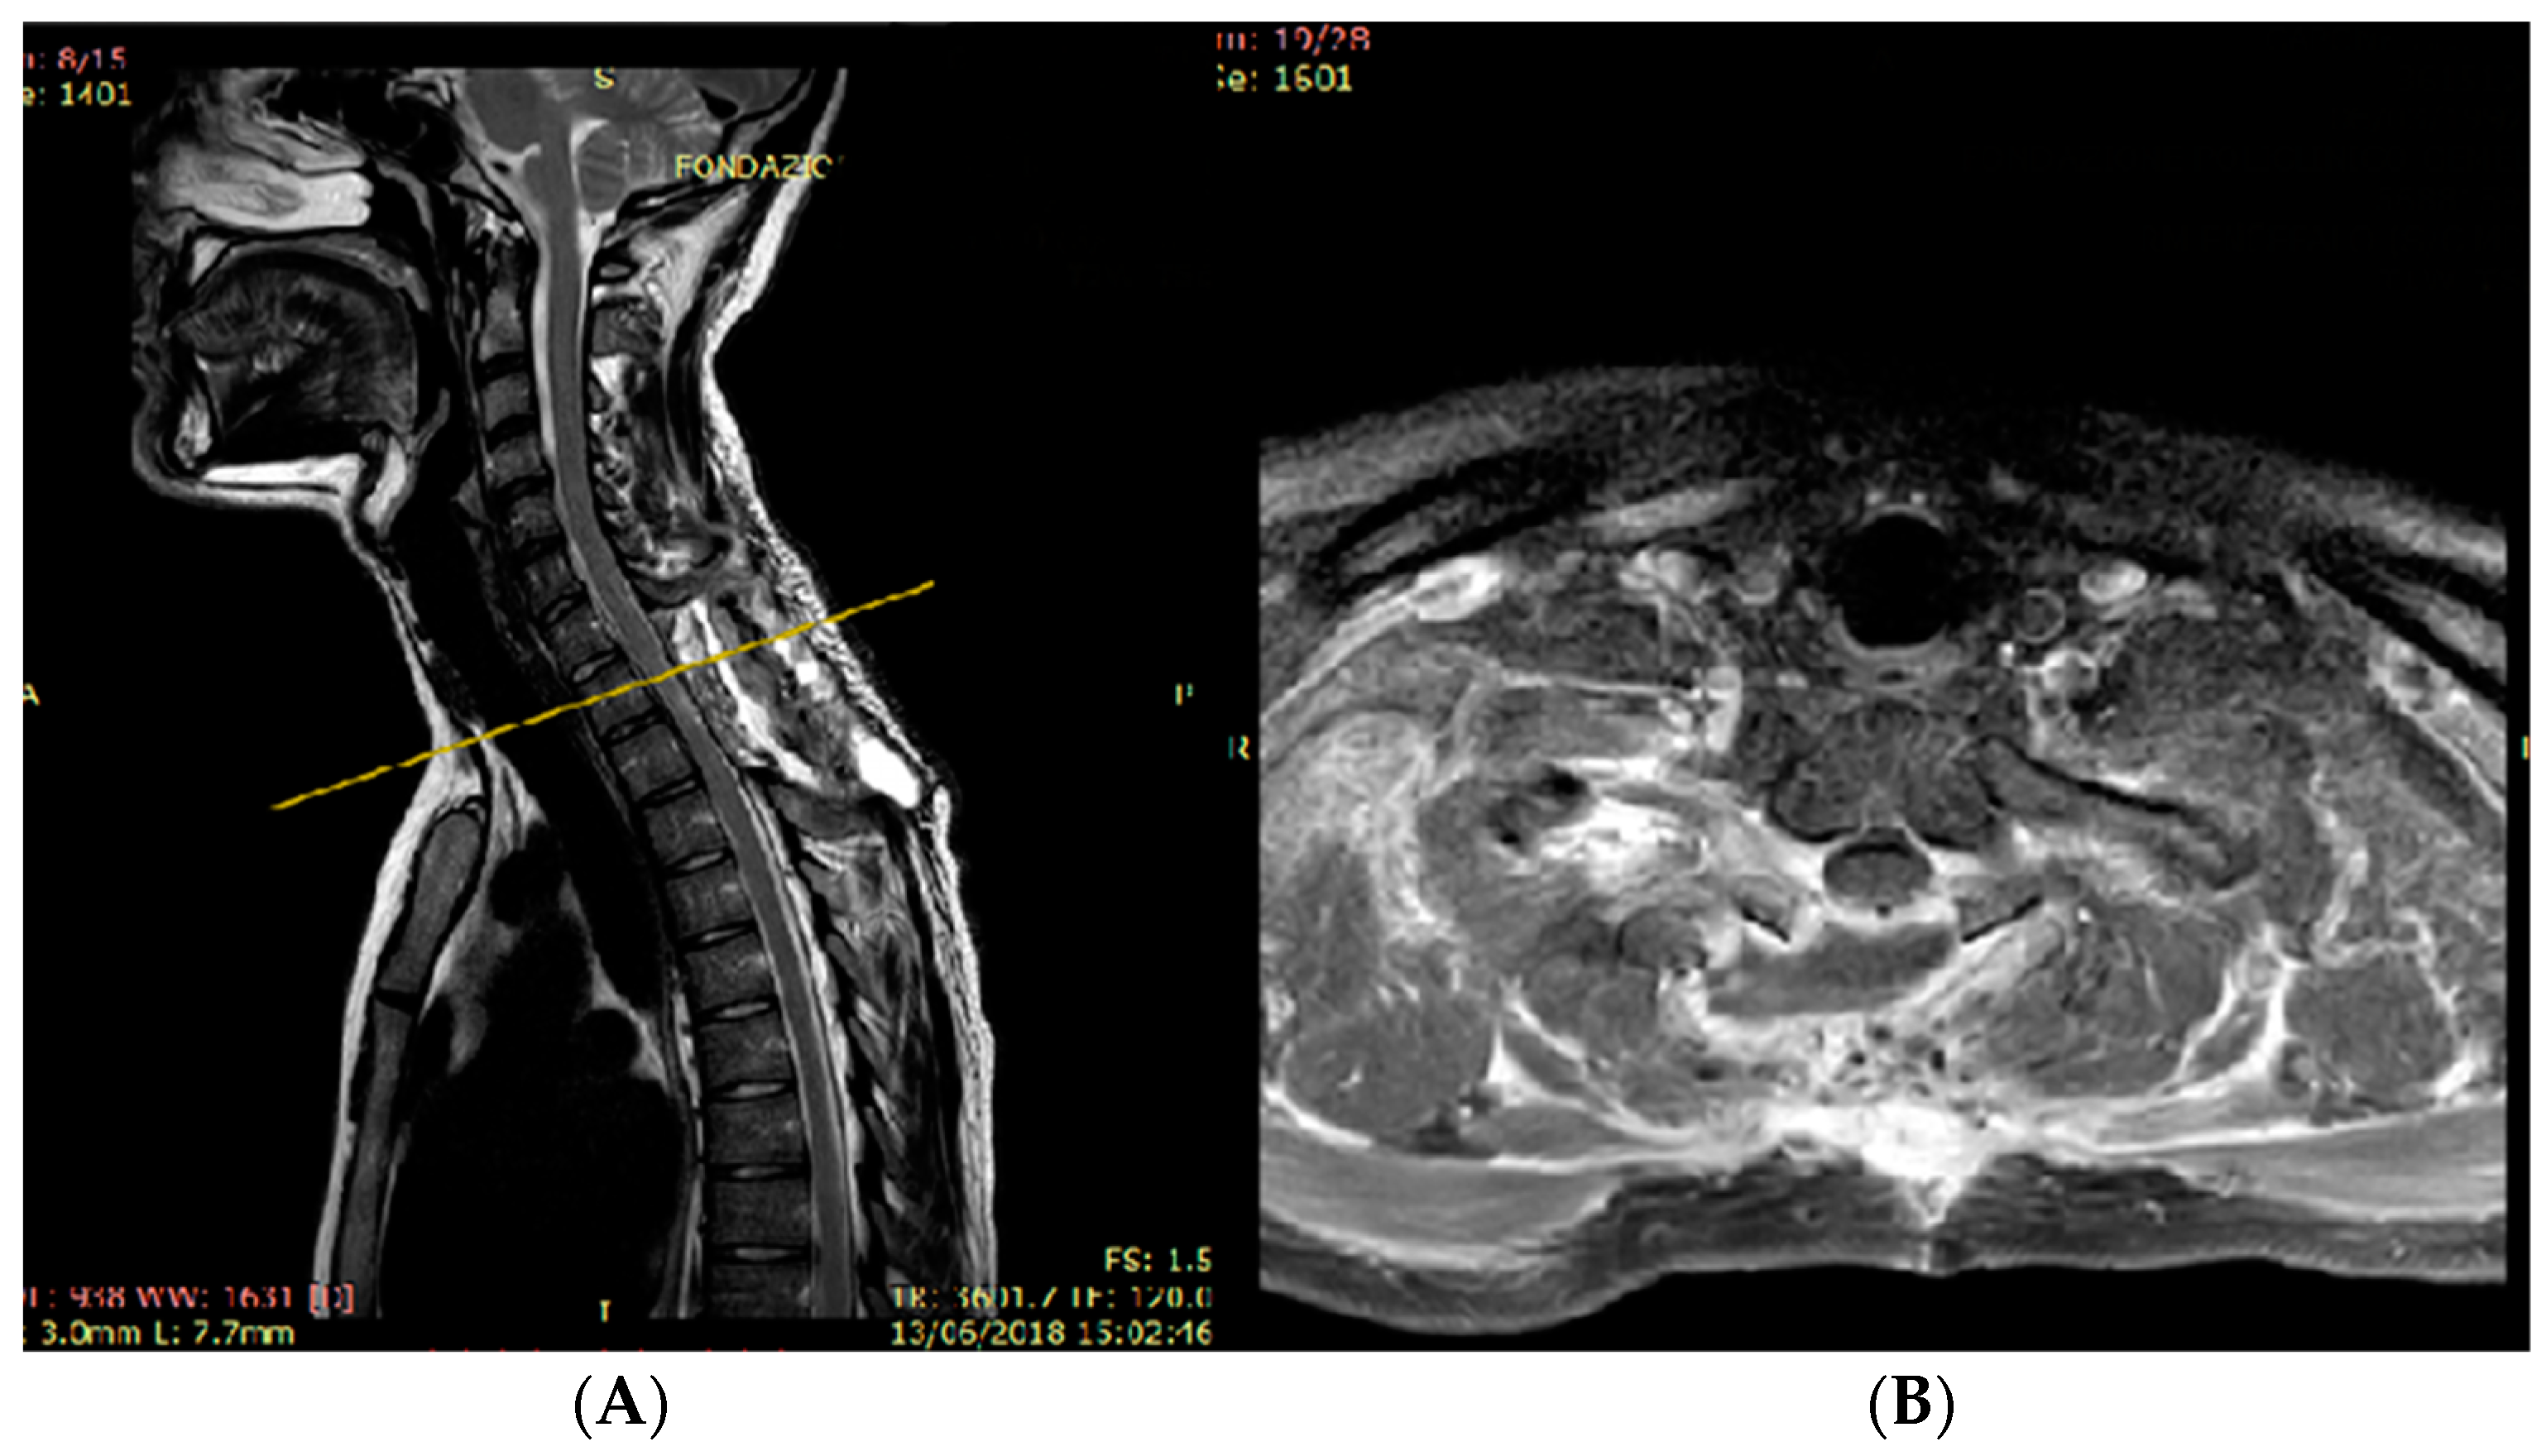

3.2. Unexpected Radiological Features in a Case of SpDG H3K27M

4.2. Radiological Finding